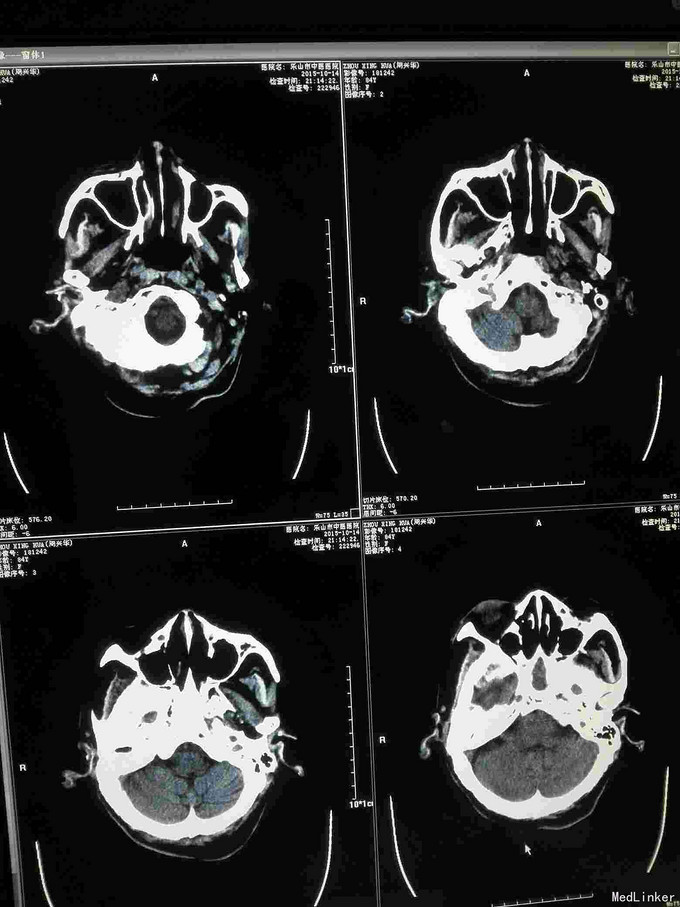

急诊CT病例

主诉 病史

昏迷不醒就诊